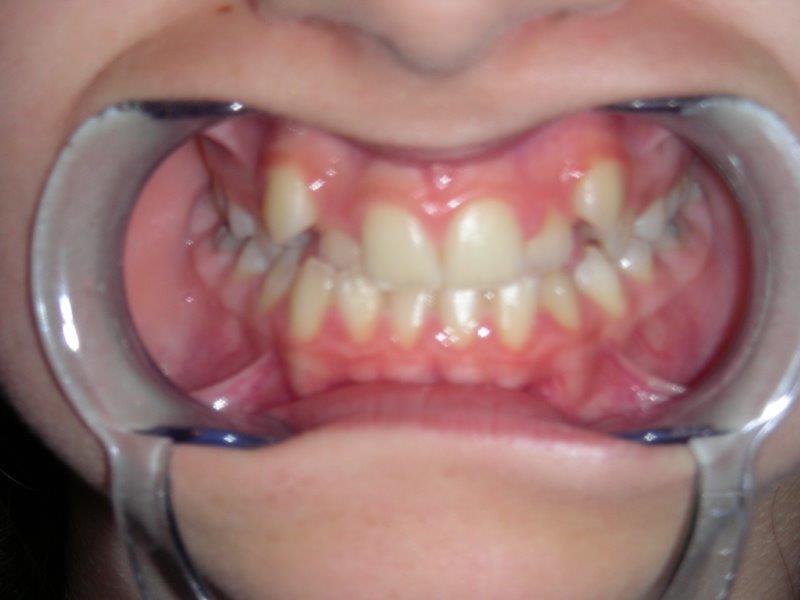

prominencia incisivos superiores PROMINENCIA DE LOS INCISIVOS SUPERIORES; riesgo de fractura en caso de golpe.

mordida cruzada dientes posteriores FALTA DE ESPACIO PARA EL LATERAL Y MORDIDA INVERSA.

mordida cruzada dientes anteriores MORDIDA INVERSA DIENTES ANTERIORES,  las paletas de arriba evolucionan por detrás de las paletas de abajo (sentido inverso).